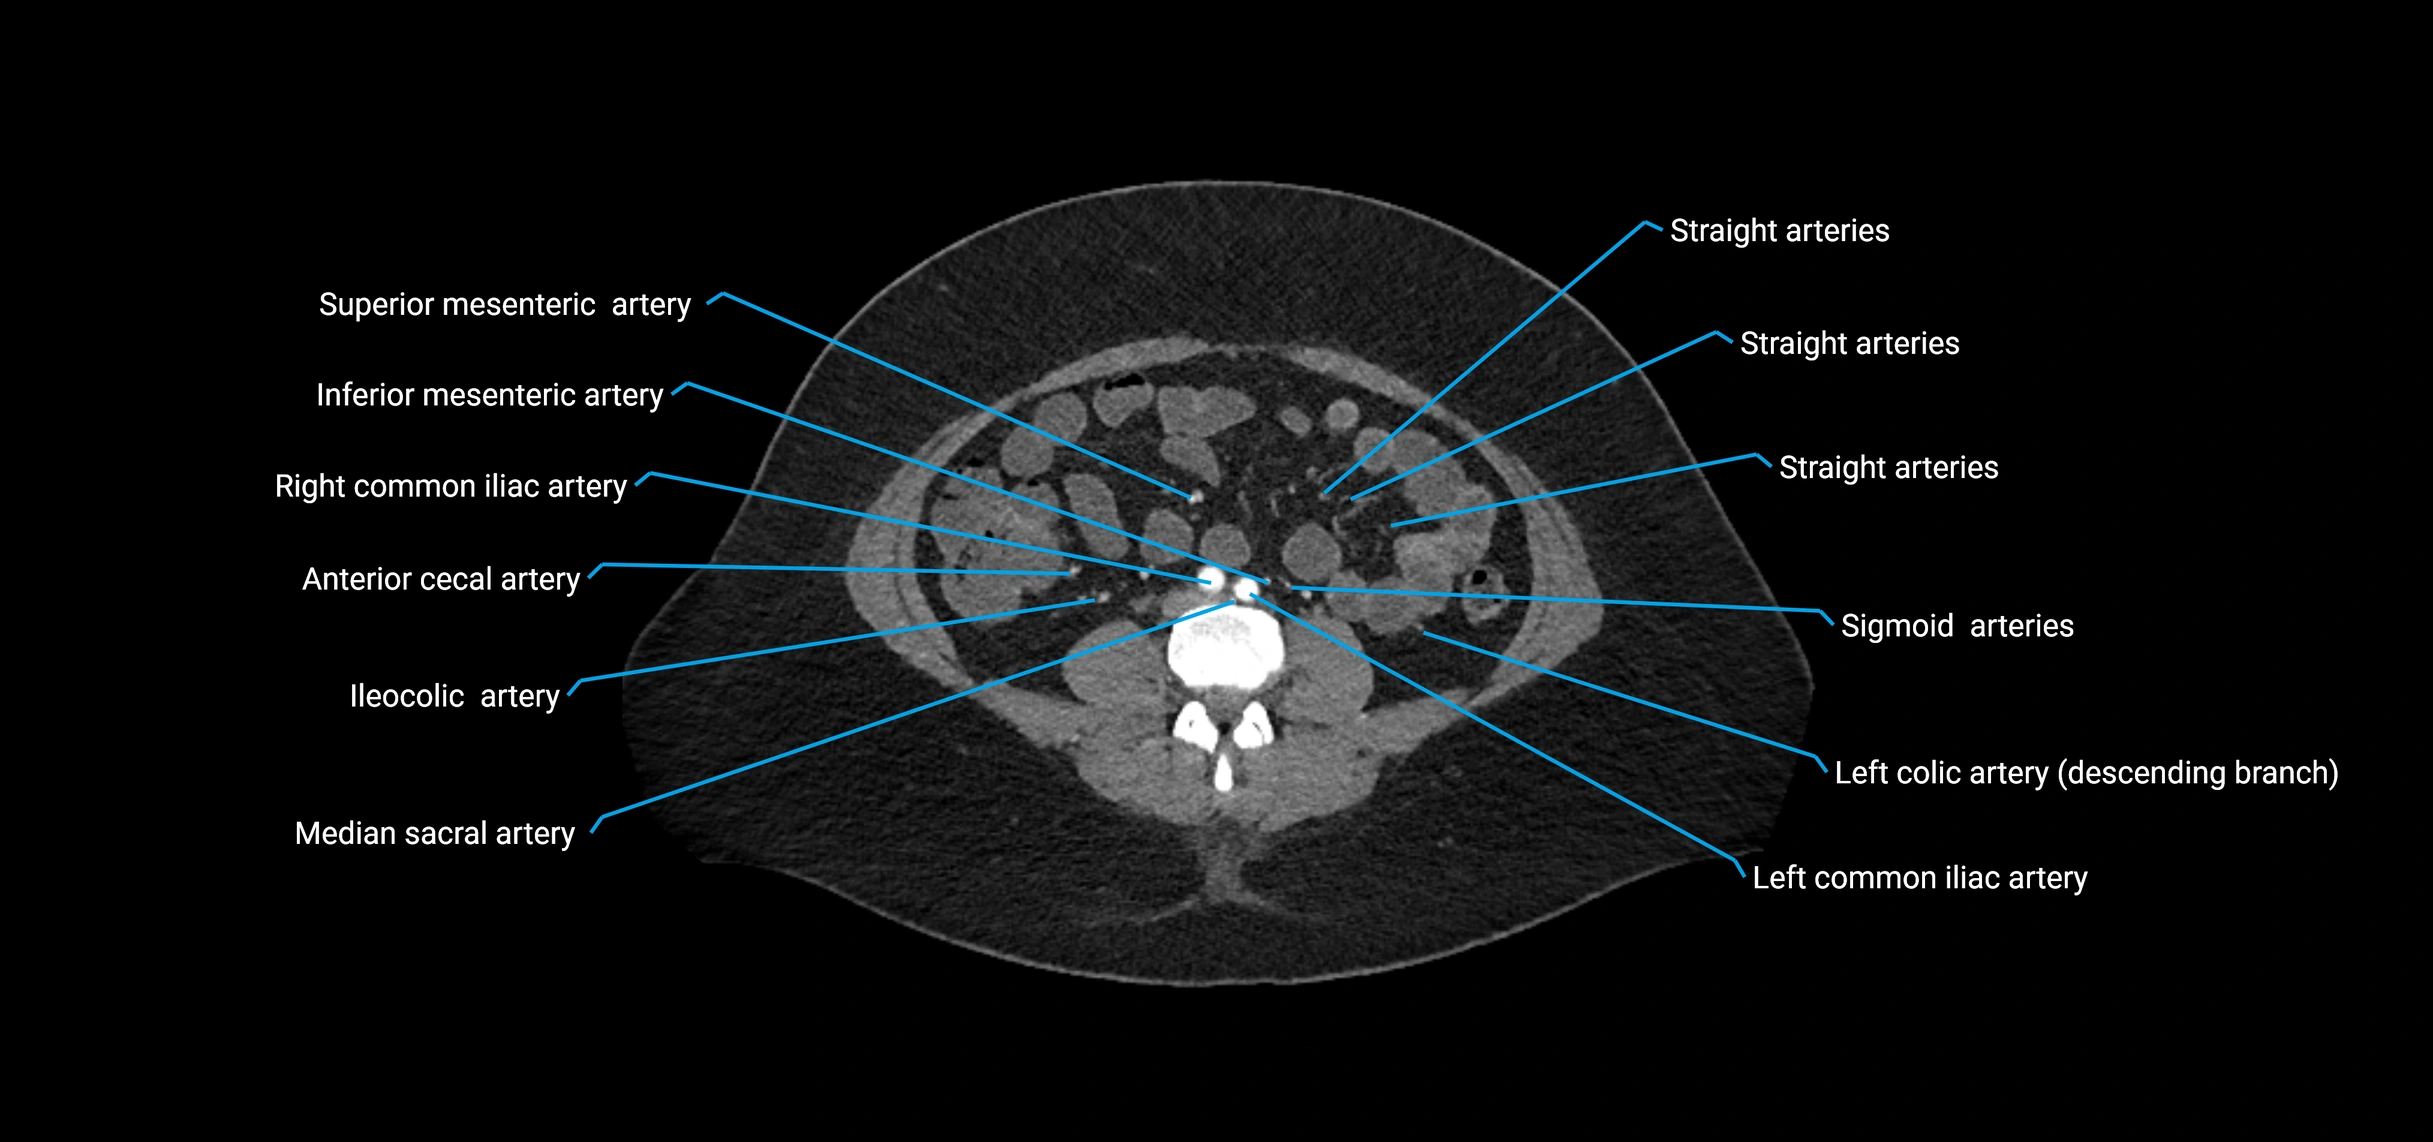

Contrast-enhanced CT (CTA):

• Gold standard for abdominal aortic imaging

• Provides excellent detail of lumen, wall, aneurysm, thrombus, and branch vessels

• Multiplanar and 3D reconstructions help in aneurysm measurement, stent graft planning, and dissection evaluation